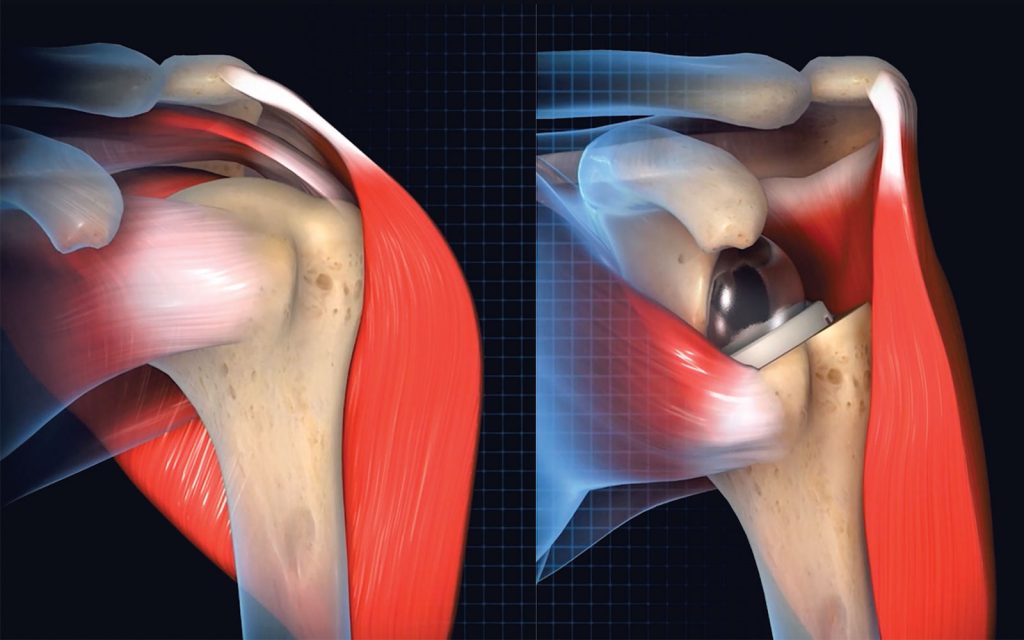

Clinical uses for PRP are many and continue to be investigated. It has been used to treat tendinopathies, partial tendon tears, complete tendon tears, arthritis, and as a surgical adjunct to aid wound healing, tendon healing and reduce pain.

Choosing the right PRP system plays a critical role in the success of your treatments. While there is no clear consensus on the best preparation, it is becoming clear that LR or LP PRP may be better in certain indications. LR-PRP may be beneficial where a strong inflammatory response is desired, such as chronic tendinopathies. LP PRP seems to be more beneficial in treating the symptoms of osteoarthritis and may help the healing of the rotator cuff tendon after surgery. A system that enables the surgeon to choose the right formulation for the right patient puts you in the best position to help.